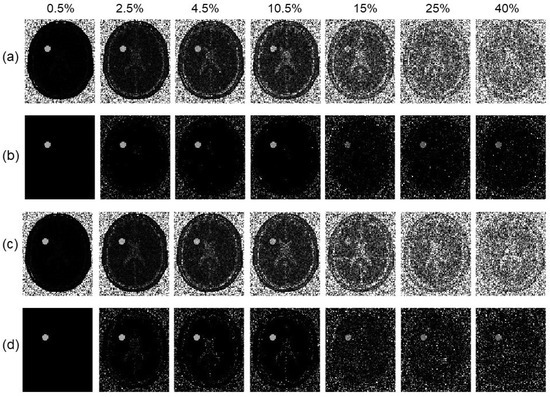

3.2. Numerical Simulations